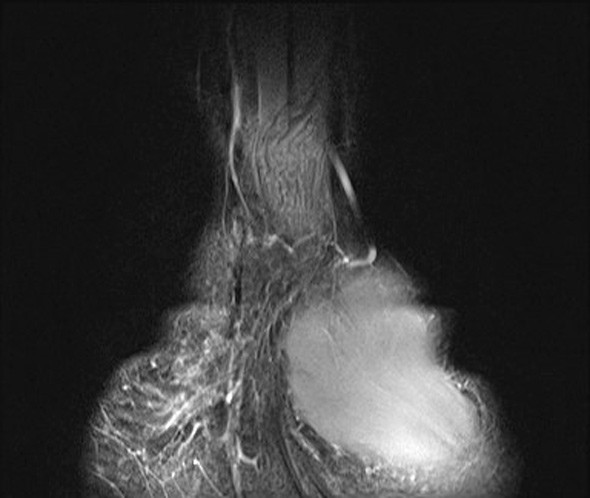

A previously healthy teenage girl was referred to the department of hand surgery with a lump on the flexor side of the left wrist. The lump had been discovered by the girl’s mother around seven years earlier and had gradually become increasingly painful. The patient described hypersensitivity to touch and numbness in the thumb, index, middle and ring fingers. Percussion over the tumour produced radiating pain and increased numbness in the same fingers. MRI showed an enlarged median nerve with a cable-like appearance due to fibrous thickening of the peri- and endoneurium and increased fat separating the roughly 15 nerve fibres (images online). The tumour was approximately 10 cm in size. A lipofibromatous hamartoma was diagnosed on the basis of the MRI findings, which are pathognomonic for the condition (1).

Surgical exploration of the tumour was performed, along with carpal tunnel decompression. At its widest point the tumour (see image) had a diameter three times the size of a normal nerve. At check-ups two and six months later, the patient was still experiencing the same pain as prior to surgery, but sensation in the fingers had improved. Neurography after two months showed moderate axonal and demyelinating sensorimotor neuropathy of the median nerve at the level of the wrist and carpus, suggesting compression neuropathy. EMG examination revealed sparse denervation activity and findings consistent with reinnervation. There were no previous examinations with which to compare the results.